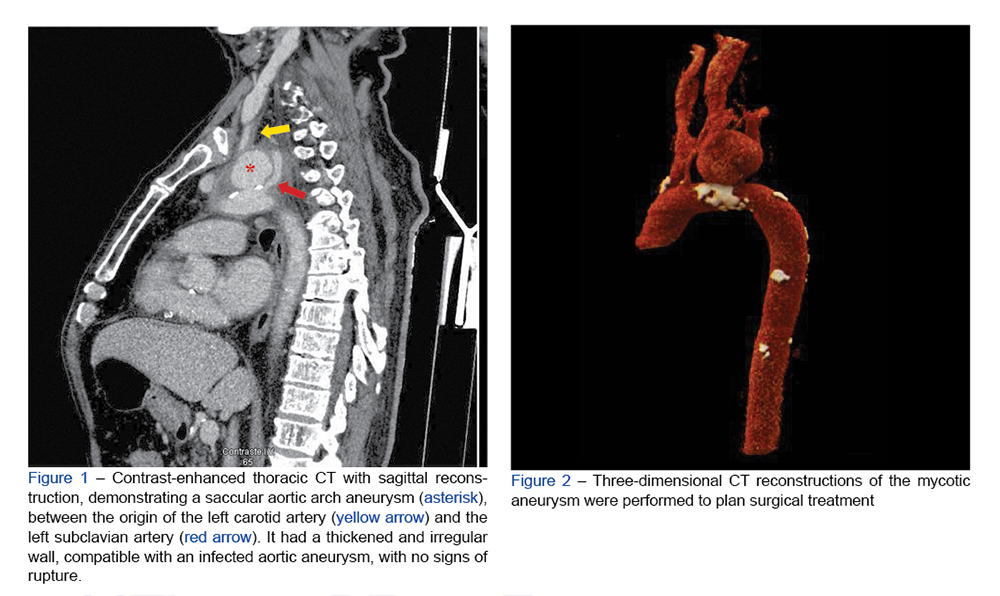

A 77-year-old man presented with a 2-week history of dysphonia and dysphagia, with concomitant anorexia, sporadic fever, and weight loss. Laboratory studies revealed n...